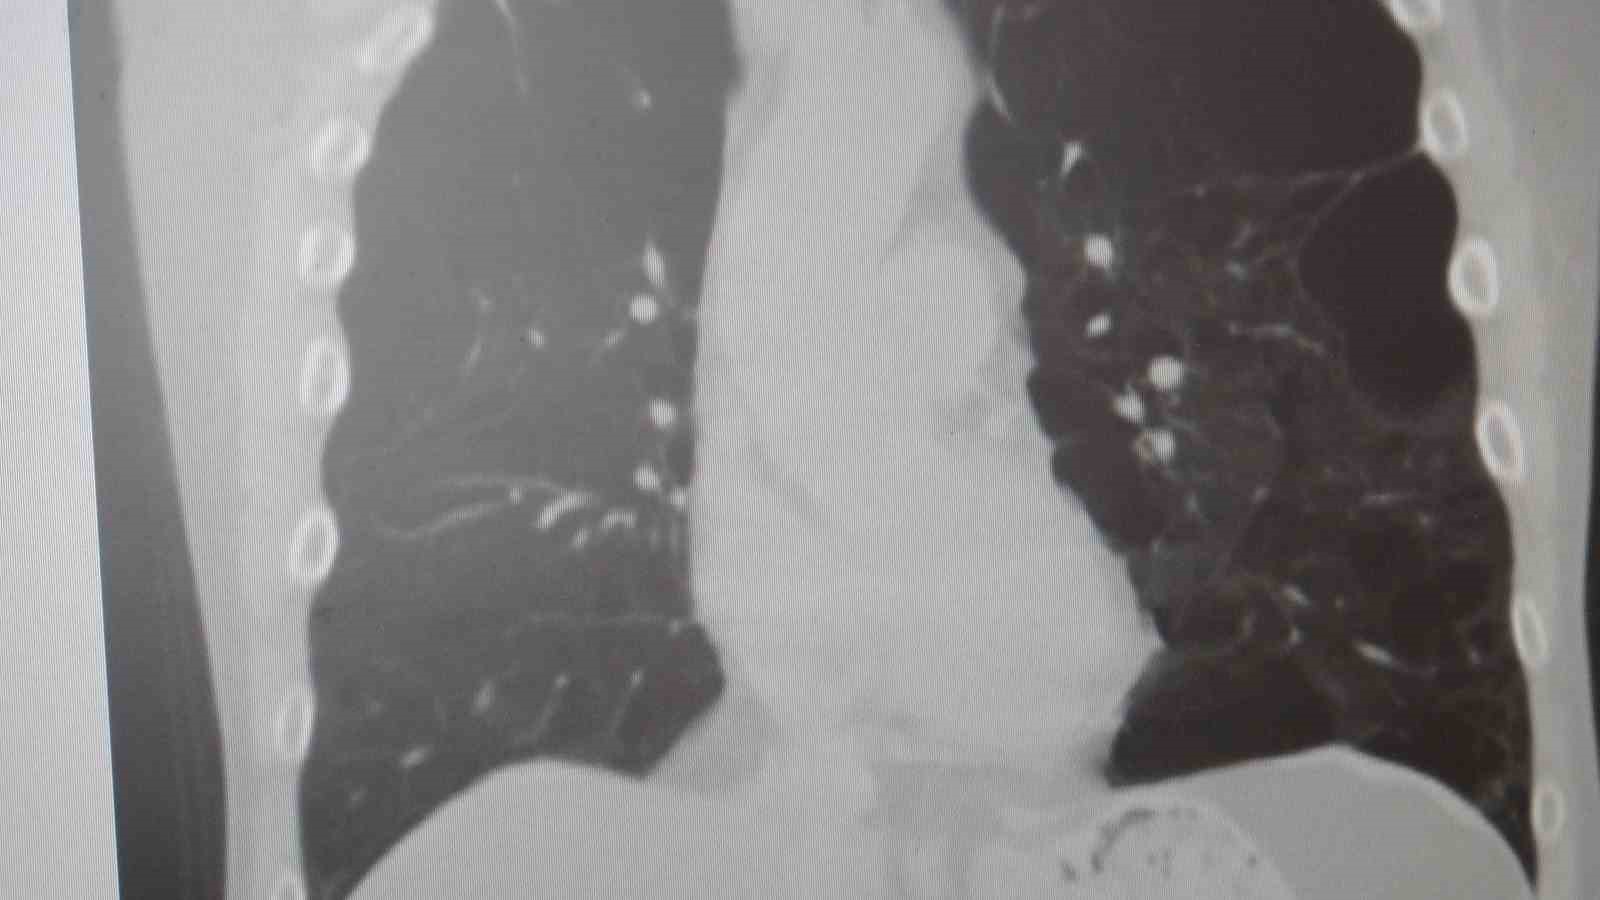

"KOAH toplumda sık görülen bir hastalıktır ve yaklaşık toplumda bunu yüzde 10 civarında görüyoruz. KOAH, zararlı maddelerin akciğeri parçalamasıyla oluşan bir rahatsızlık ve bunun da en önemli nedeni sigara. Vakaların aşağı yukarı yüzde 85’i sigara kullanımından kaynaklıdır. Bunun dışında hava kirliliği, iş yerlerinde kimyasal maddelere maruz kalma ve enfeksiyonlar da yine KOAH’ın nedenleri arasındadır. KOAH’ın önemi şu; bugün Dünya Sağlık Örgütü’nün (DSÖ) dünyada insanları öldüren hastalıklar listesinde ilk 10’da 4’üncü sırada yer alıyor. KOAH önlenebilir bir rahatsızlıktır; sigaranın bırakılmasıyla birlikte tamamen ortadan kalkacaktır."

KOAH’ın akciğer dokusunu tahrip eden bir hastalık olduğunu ve bu nedenle de hastaların enfeksiyona açık hale geldiğine dikkat çeken Karakurt, "Akciğer dokusunun tahrip olduğu her durumda hastaların enfeksiyona karşı eğilimi artar ve enfeksiyona yakalandıkları zaman bunun geçmesi güç olur. KOAH’lı hastalar zatürre geçirdikleri zaman öksürük ve balgam artışı gibi bir takım belirtiler gelişir. Ayrıca ateşin 38,5 derecenin üstüne çıkması, nefes darlığının artması, titremeyle birlikte ateşin yükselmesi ve bir takım bilinç bozukluğu gibi belirtiler hastanın zatürre olduğunu gösterebilir. Bu nedenle hastaların erkenden doktora başvurmaları önemlidir" şeklinde konuştu.